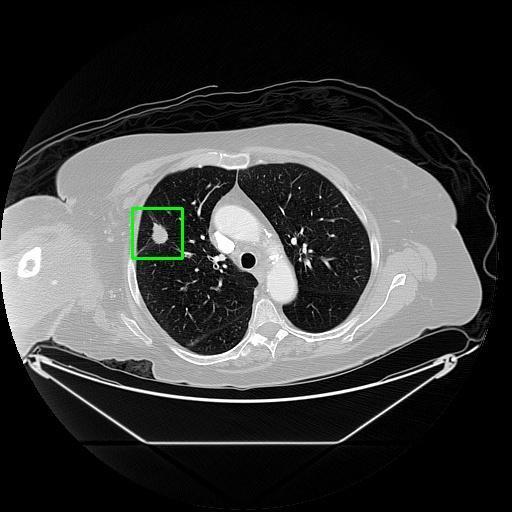

We developed an AI-based system using deep learning models for analyzing lung CT scans to detect and classify pulmonary nodules. We chose the YOLOv11 architecture for its enhanced object detection capability and adapted it specifically for medical imaging, incorporating pixel-level precision and severity classification.

Classification into three severity levels with colored bounding boxes.

Successfully built and deployed an AI model (YOLOv11) capable of detecting lung nodules in CT scans with high accuracy and real-time performance.

Designed a severity classification system that categorizes nodules into null, moderate, and severe using colored bounding boxes, assisting in rapid clinical decision-making.